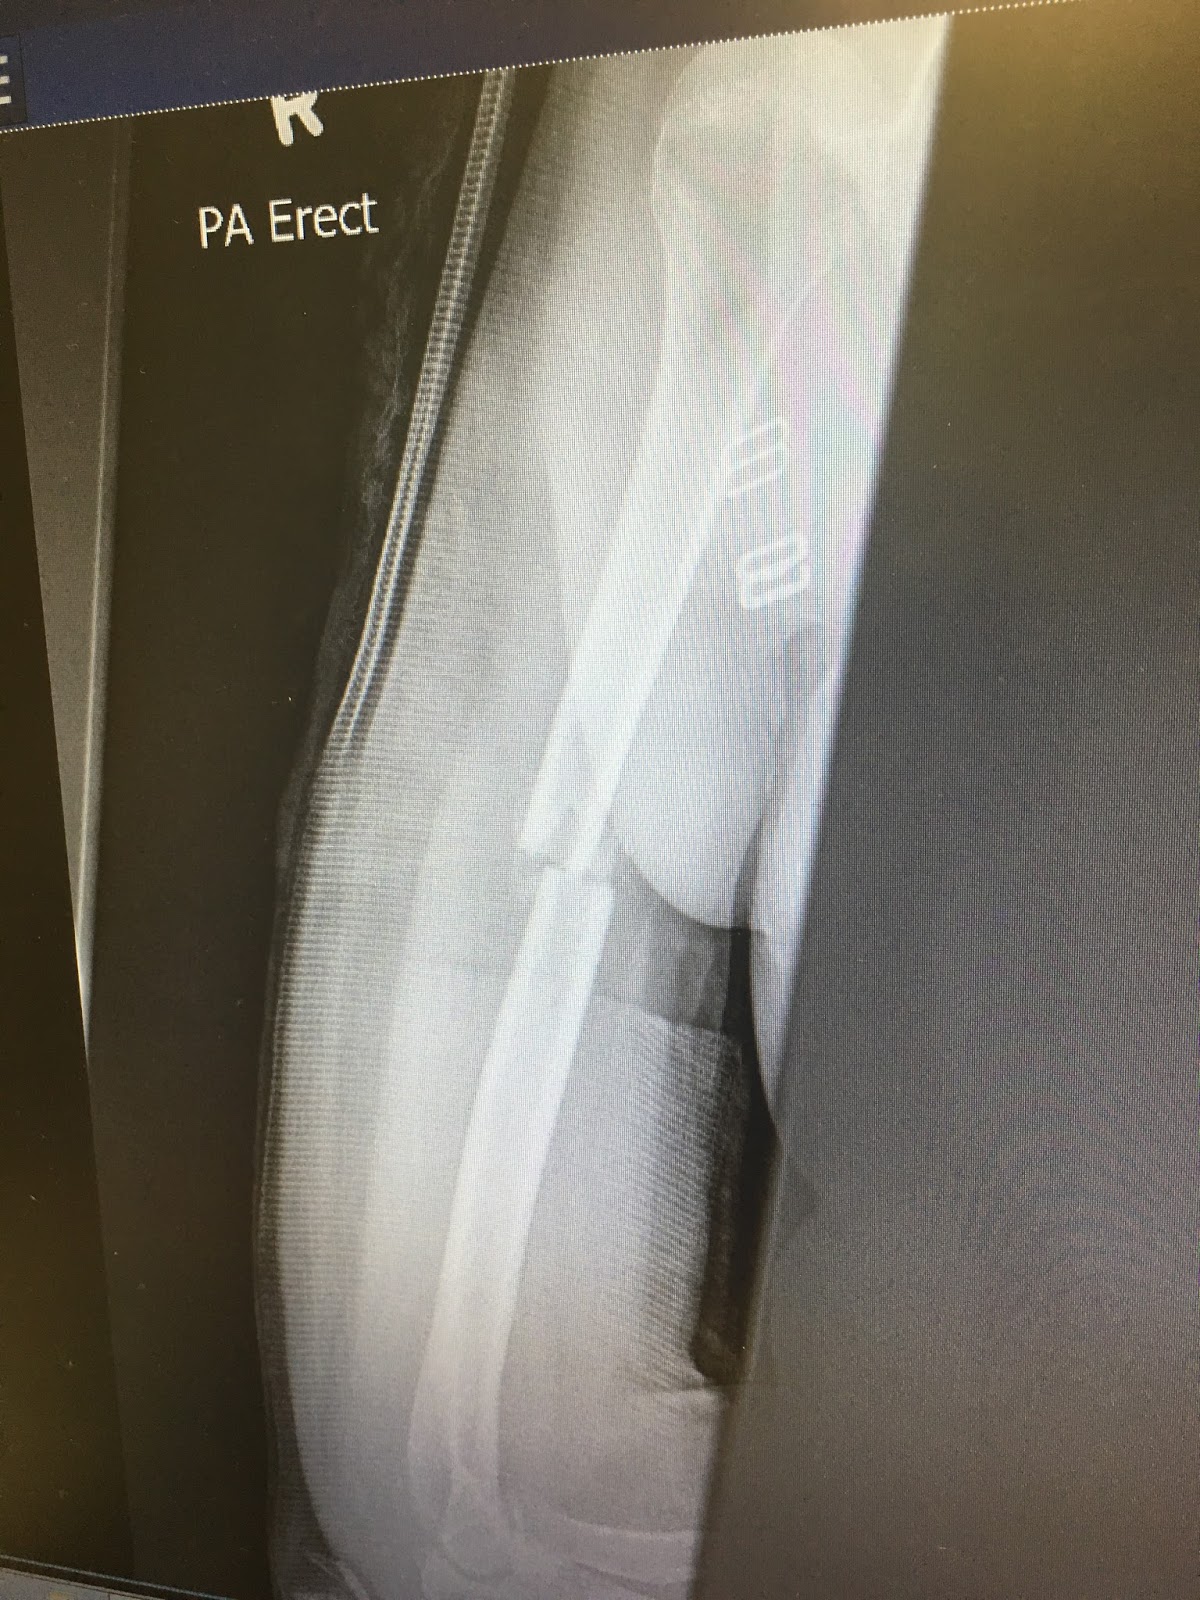

Some of you asked me if I could share the last X-ray I had taken.

Here it is and also a photo of my plastered and bandaged arm.

My arm gets very heavy if I walk for a long time.

Next week I go and visit the bone doctor. Yay.....

I have my fingers crossed the plaster and bandages might be taken off.

Can you see the two bones starting to mend?